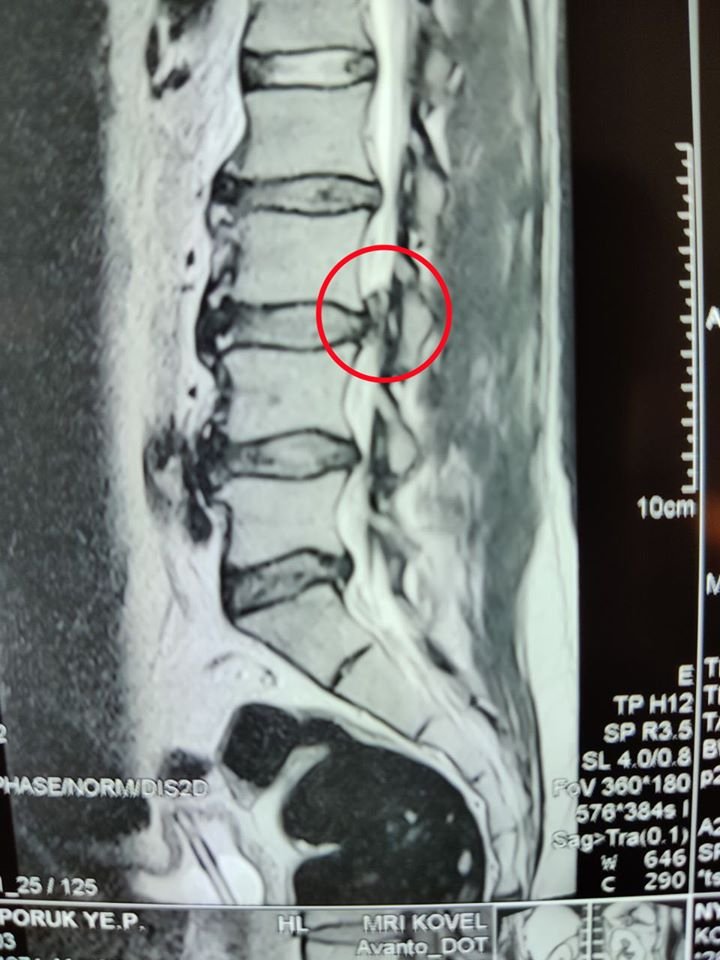

Лікарі Ковельського МТМО прооперували чоловіка, у якого діагностували секвестровану грижу L3-L4 з критичним стенозом спинномозкового каналу.

Чоловік 46 років був скерований з Камінь-Каширського району з вираженими болями в попереку, які іррадіювали в нижні кінцівки, та порушенням функції тазових органів.

Медики в ургентному порядку провели видалення секветрованої грижі справа (мікродискектомія L3-L4 справа). Наразі пацієнт почуває себе чудово і вже може вільно пересуватися.